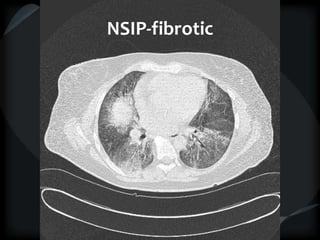

Reticular Pattern - NSIP

inflammation and fibrosis

 Predominantly basilar

 Significant ground glass

 Subpleural sparing low sensitivity, high specificity

 No honeycombing, some cystic change

 Traction Bronchiectasis

Diagnostic accuracy 50%

 Cellular NSIP

 Fibrotic NSIP

 Associated with CVD

 Undifferentiated CVD – T. King

NSIP- cellular

NSIP-fibrotic